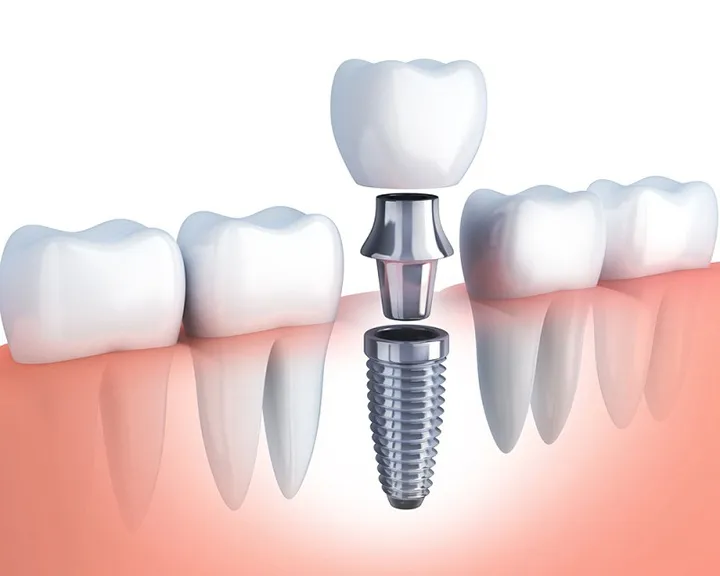

Điều trị nội nha hay chữa tủy là kĩ thuật được áp dụng để điều trị viêm tủy răng không hồi phục. Kỹ thuật này được thực hiện với mục đích làm sạch tủy răng bị tổn thương. Sau đó sát khuẩn rồi trạm bít khoang tủy bằng vật liệu nhân tạo.

Ngoài ra điều trị nội nha còn được áp dụng để điều trị răng sâu, tủy, viêm nha chu lan đến tủy, chấn thương răng. Đây là kĩ thuật phức tạp. Điều này đòi hỏi sự hỗ trợ của máy móc thiết bị và nha sĩ có tay nghề cao. Quy trình điều trị nội nha bao gồm các bước như sau

- Khám và chụp X – quang để đánh giá mức độ xương hàm và có phương pháp điều trị cụ thể.

- Gây tê bằng thuốc để loại trừ cảm giác đau.

- Khoan răng để mở buồng tủy rồi lấy sạch phần tủy bị viêm nhiễm. Sau đó bơm rửa nhiều lần để tránh hiện tượng sót tủy.

- Sát khuẩn và làm khô khoang tủy đồng thời tạo hình ống tủy bằng vật liệu nhân tạo.

- Với các răng có lỗ sâu lớn bác sĩ có thể yêu cầu bệnh nhân bọc răng sứ. Từ đó tránh răng bị hở tủy sứt mẻ trong quá trình ăn uống.